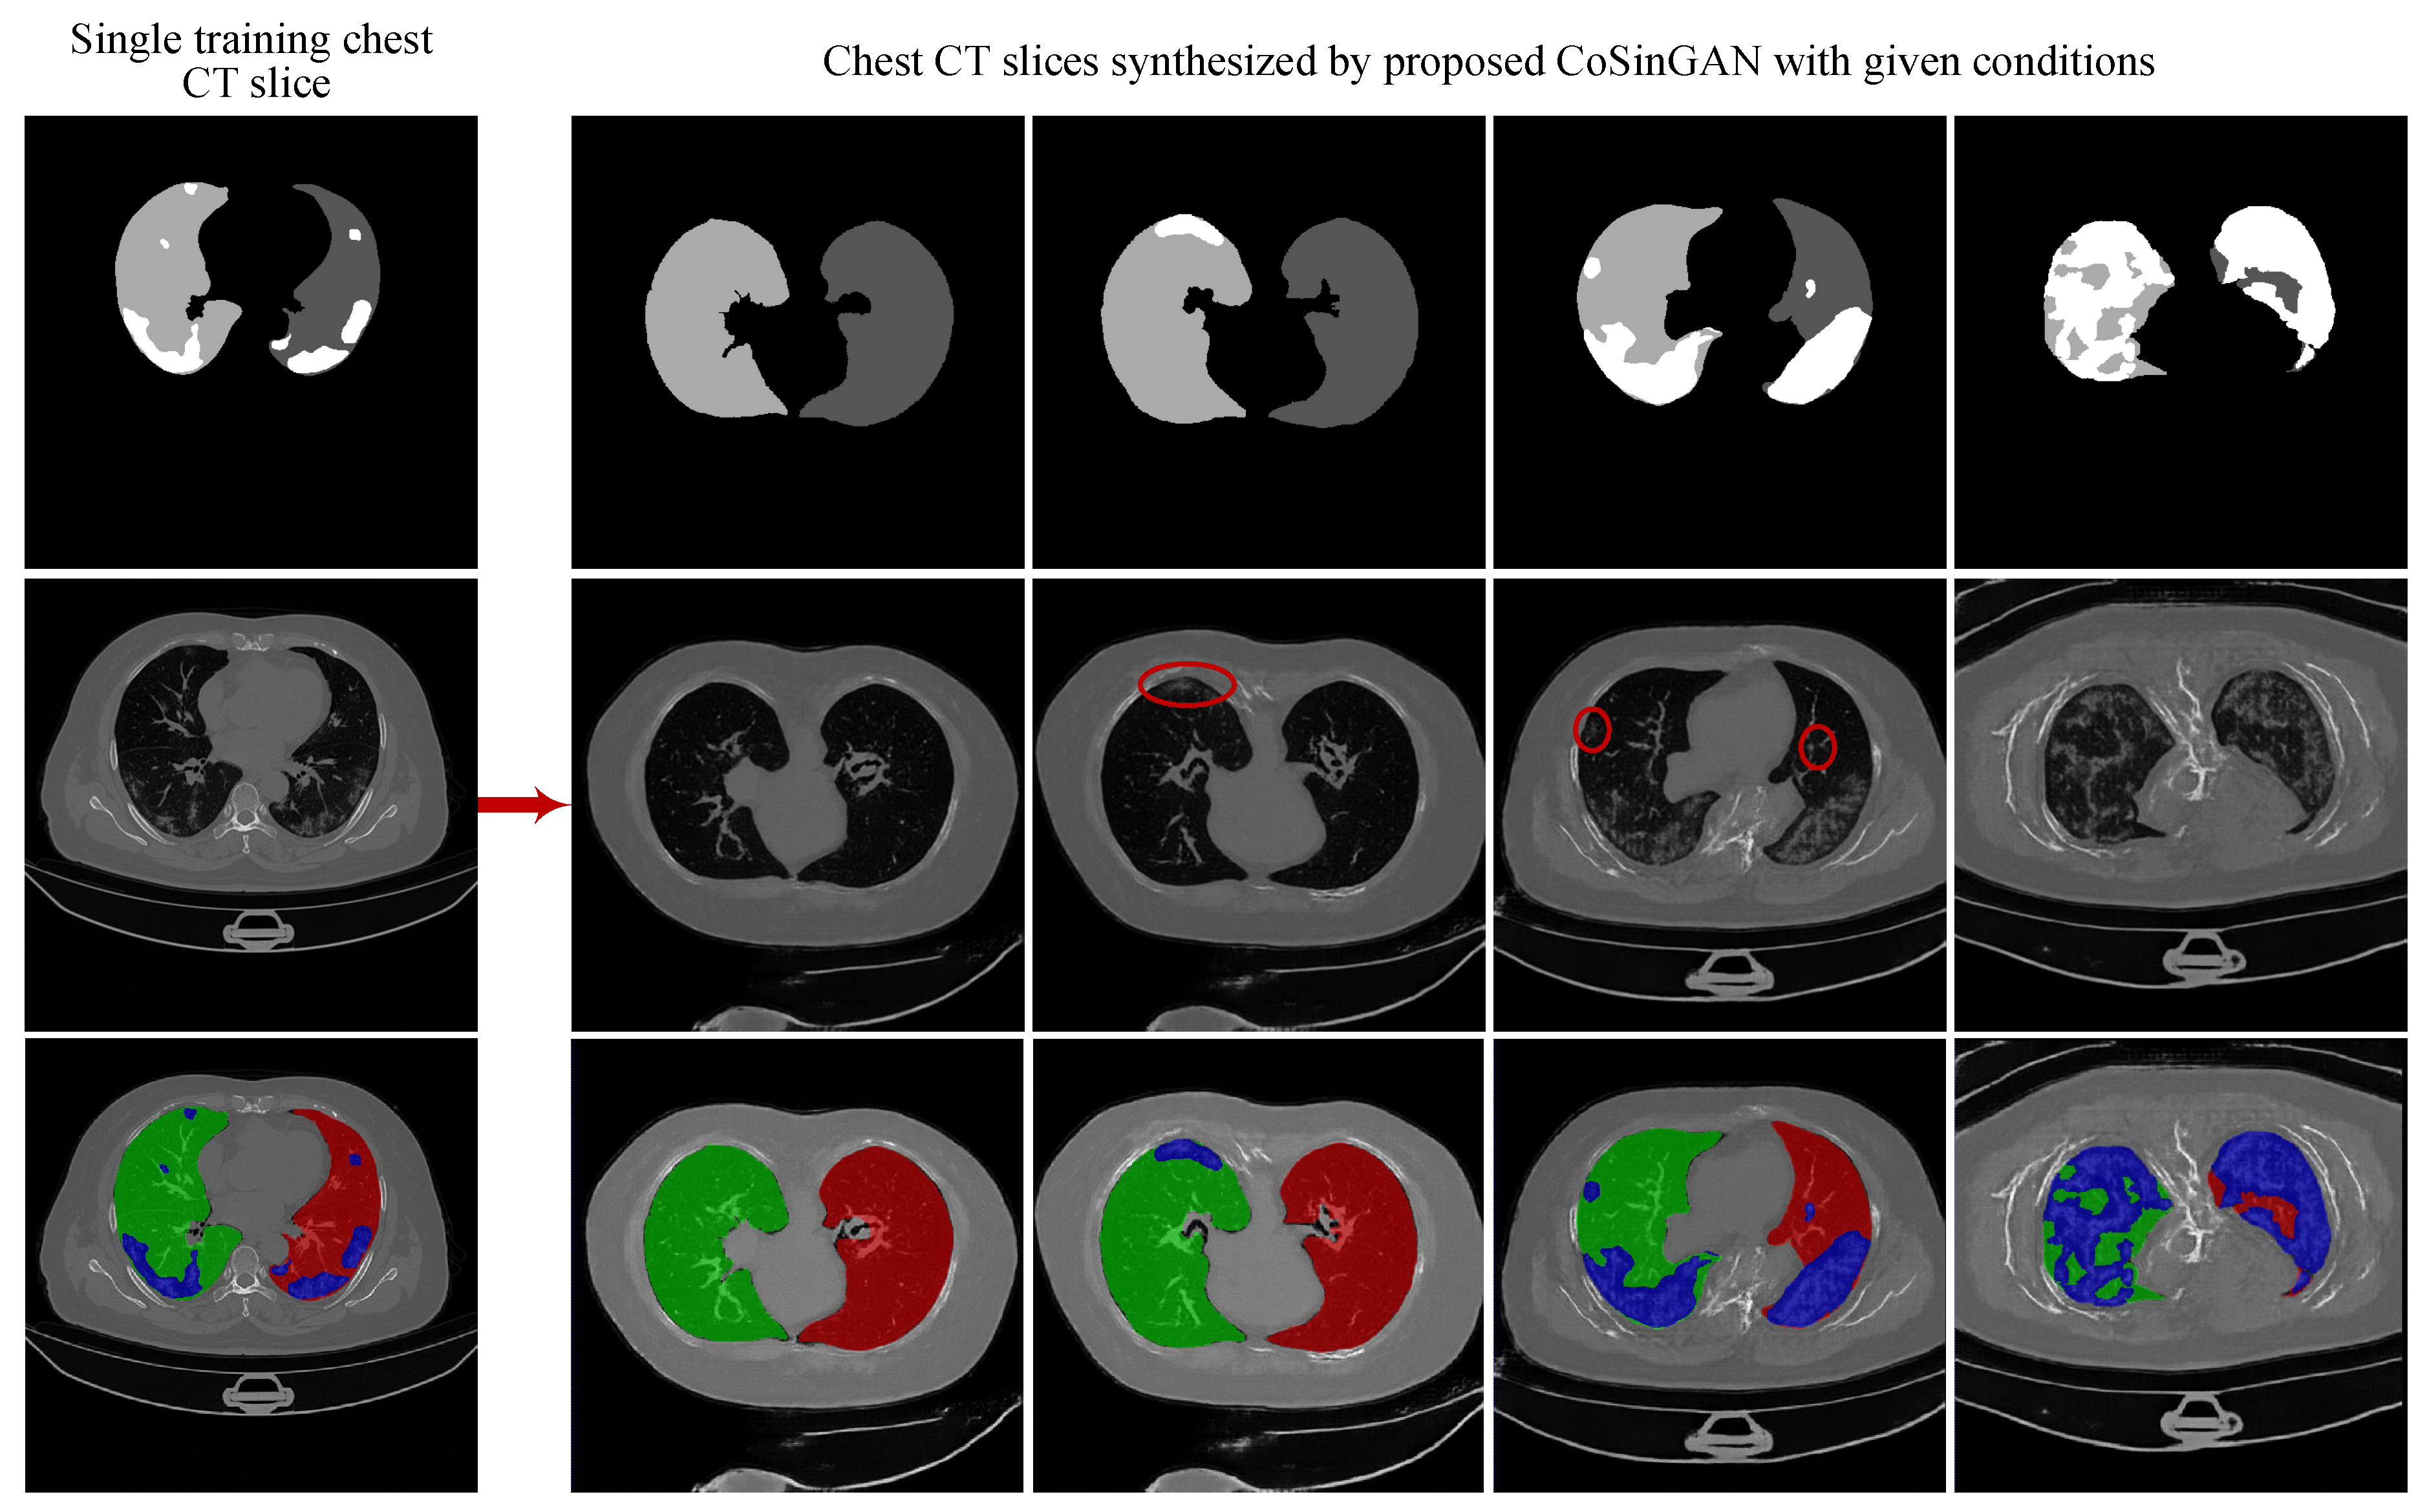

3.1. Experiments on Synthesizing Radiological Images

3.1.4. Evaluation on the Ability of CoSinGAN in Generating Diverse Samples

- Qualitative comparison